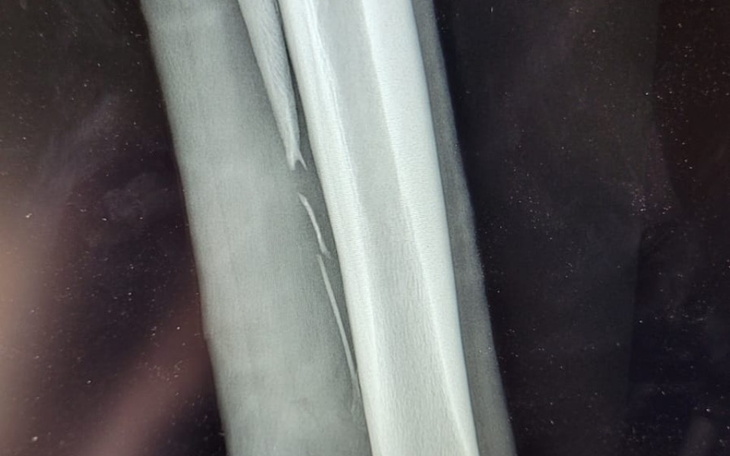

Dzień dobry, długo zastanawiałam się czy założyć zbiórkę, lecz kilka osób mnie do tego pchnęło, więc opowiem o naszej sytuacji. Z Fortunką razem spędziłyśmy już 8 lat. Była koniem „wyrzuconym” ze stajni prosto na koński targ, chuda, licha, ledwo stojąca na nogach. Trafiła do mnie i tak zaczęła się nasza przygoda. Teraz jest koniem pełnym energii i często dającym nieźle popalić, ale to moja przyjaciółka i członek rodziny i darze ją bardzo wielkim uczuciem.Fortunie w czerwcu zdarzył się niefortunny wypadek. Jak zobaczyłam jej nogę odrazu wiedziałam, że to coś poważniejszego. Zadzwoniłam po naszego weterynarza, który przyjechał następnego dnia i diagnoza- złamana kość rysikowa, potrzaskana na kawałki. Wiedziałam odrazu, że nie ominie nas operacja. Fortunie sprawia to ból, noga jest tkliwa a odłamki kości podrażniają od środka. Operacje mamy ustaloną na 12.07, koszt to około 5 tys wraz z pobytem w klinice. Dlatego zwracam się z prośba o pomoc, wypadek wydarzył się chyba w najgorszym możliwym dla mnie okresie. Będę naprawdę wdzięczna z każda wpłatę i udostępnienie. A za Fortunę trzymajcie kciuki żeby cały zabieg oraz rehabilitacja poszła po naszej myśli! 🐴🐴